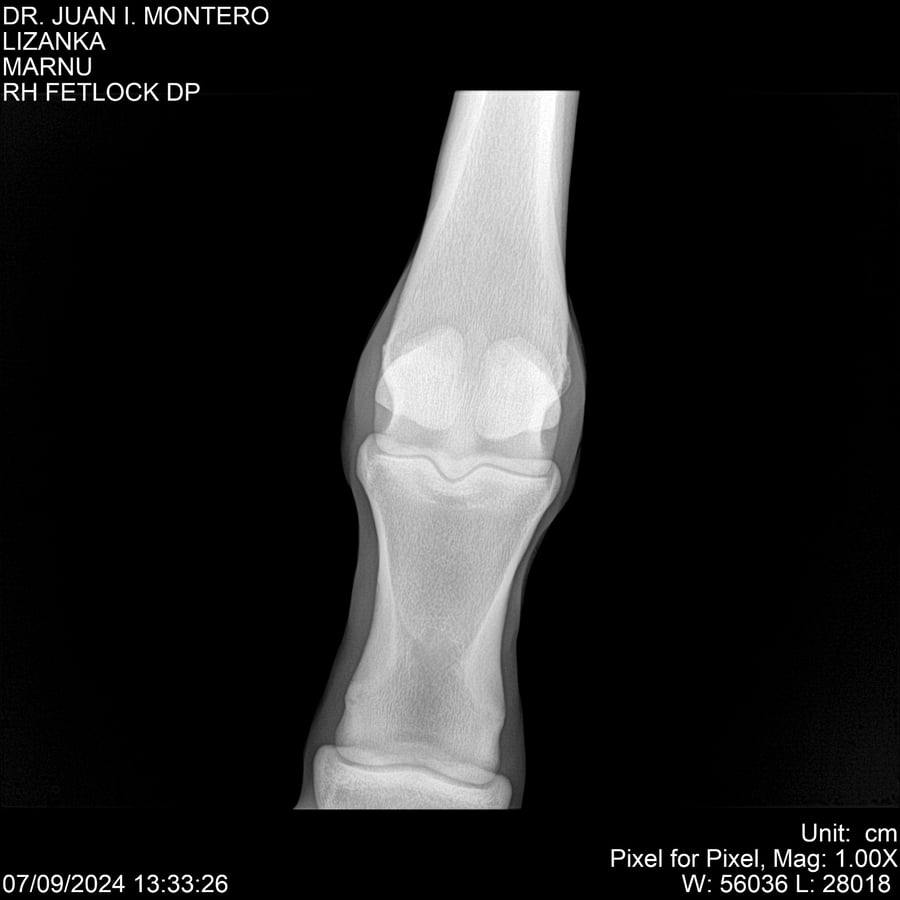

LOTE 18, LIZANKA Lote Anterior Volver al remate Lote Siguiente Ficha Contacto Montevideo - Ficha del Lote Identificador: #282512 Categoría: Yeguarizos Montevideo - 62 Visualizaciones ClicData Contacto Empresa: Abelenda N. R., Walter Hugo Nombre*: Teléfono* : E-mail* : Mensaje Enviar Registrese gratis Este contenido Exclusivo está disponible sólo para usuarios registrados Ingresar